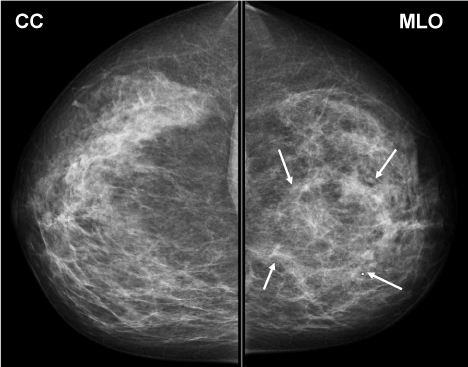

The patient is a 38 year woman referred urgently by her gynaecologist with a left breast mass that had rapidly filled the upper inner quadrant (UIQ) with concerns for inflammatory breast cancer. The patient complained of pain and mild redness of the skin over the anterior breast. She denied trauma, fever, chills, nipple discharge, or skin ulceration. The breast exam revealed obvious breast asymmetry due to a 15 × 15 cm mass extending from the UIQ to an area below the nipple-areola complex. It was firm, irregular, with mild skin edema, and mobile relative to the chest wall (Figure 1). There was no axillary adenopathy. Mammography (Figure 2), ultrasound, and biopsies were obtained. Pathology reported acute and chronic mastitis with granulomatous reaction and negative for carcinoma.

Figure 2. Pretreatment Diagnostic mammogram. Arrows denote the margins of the mass